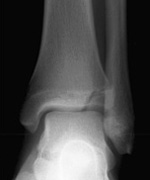

What abnormality is shown here?